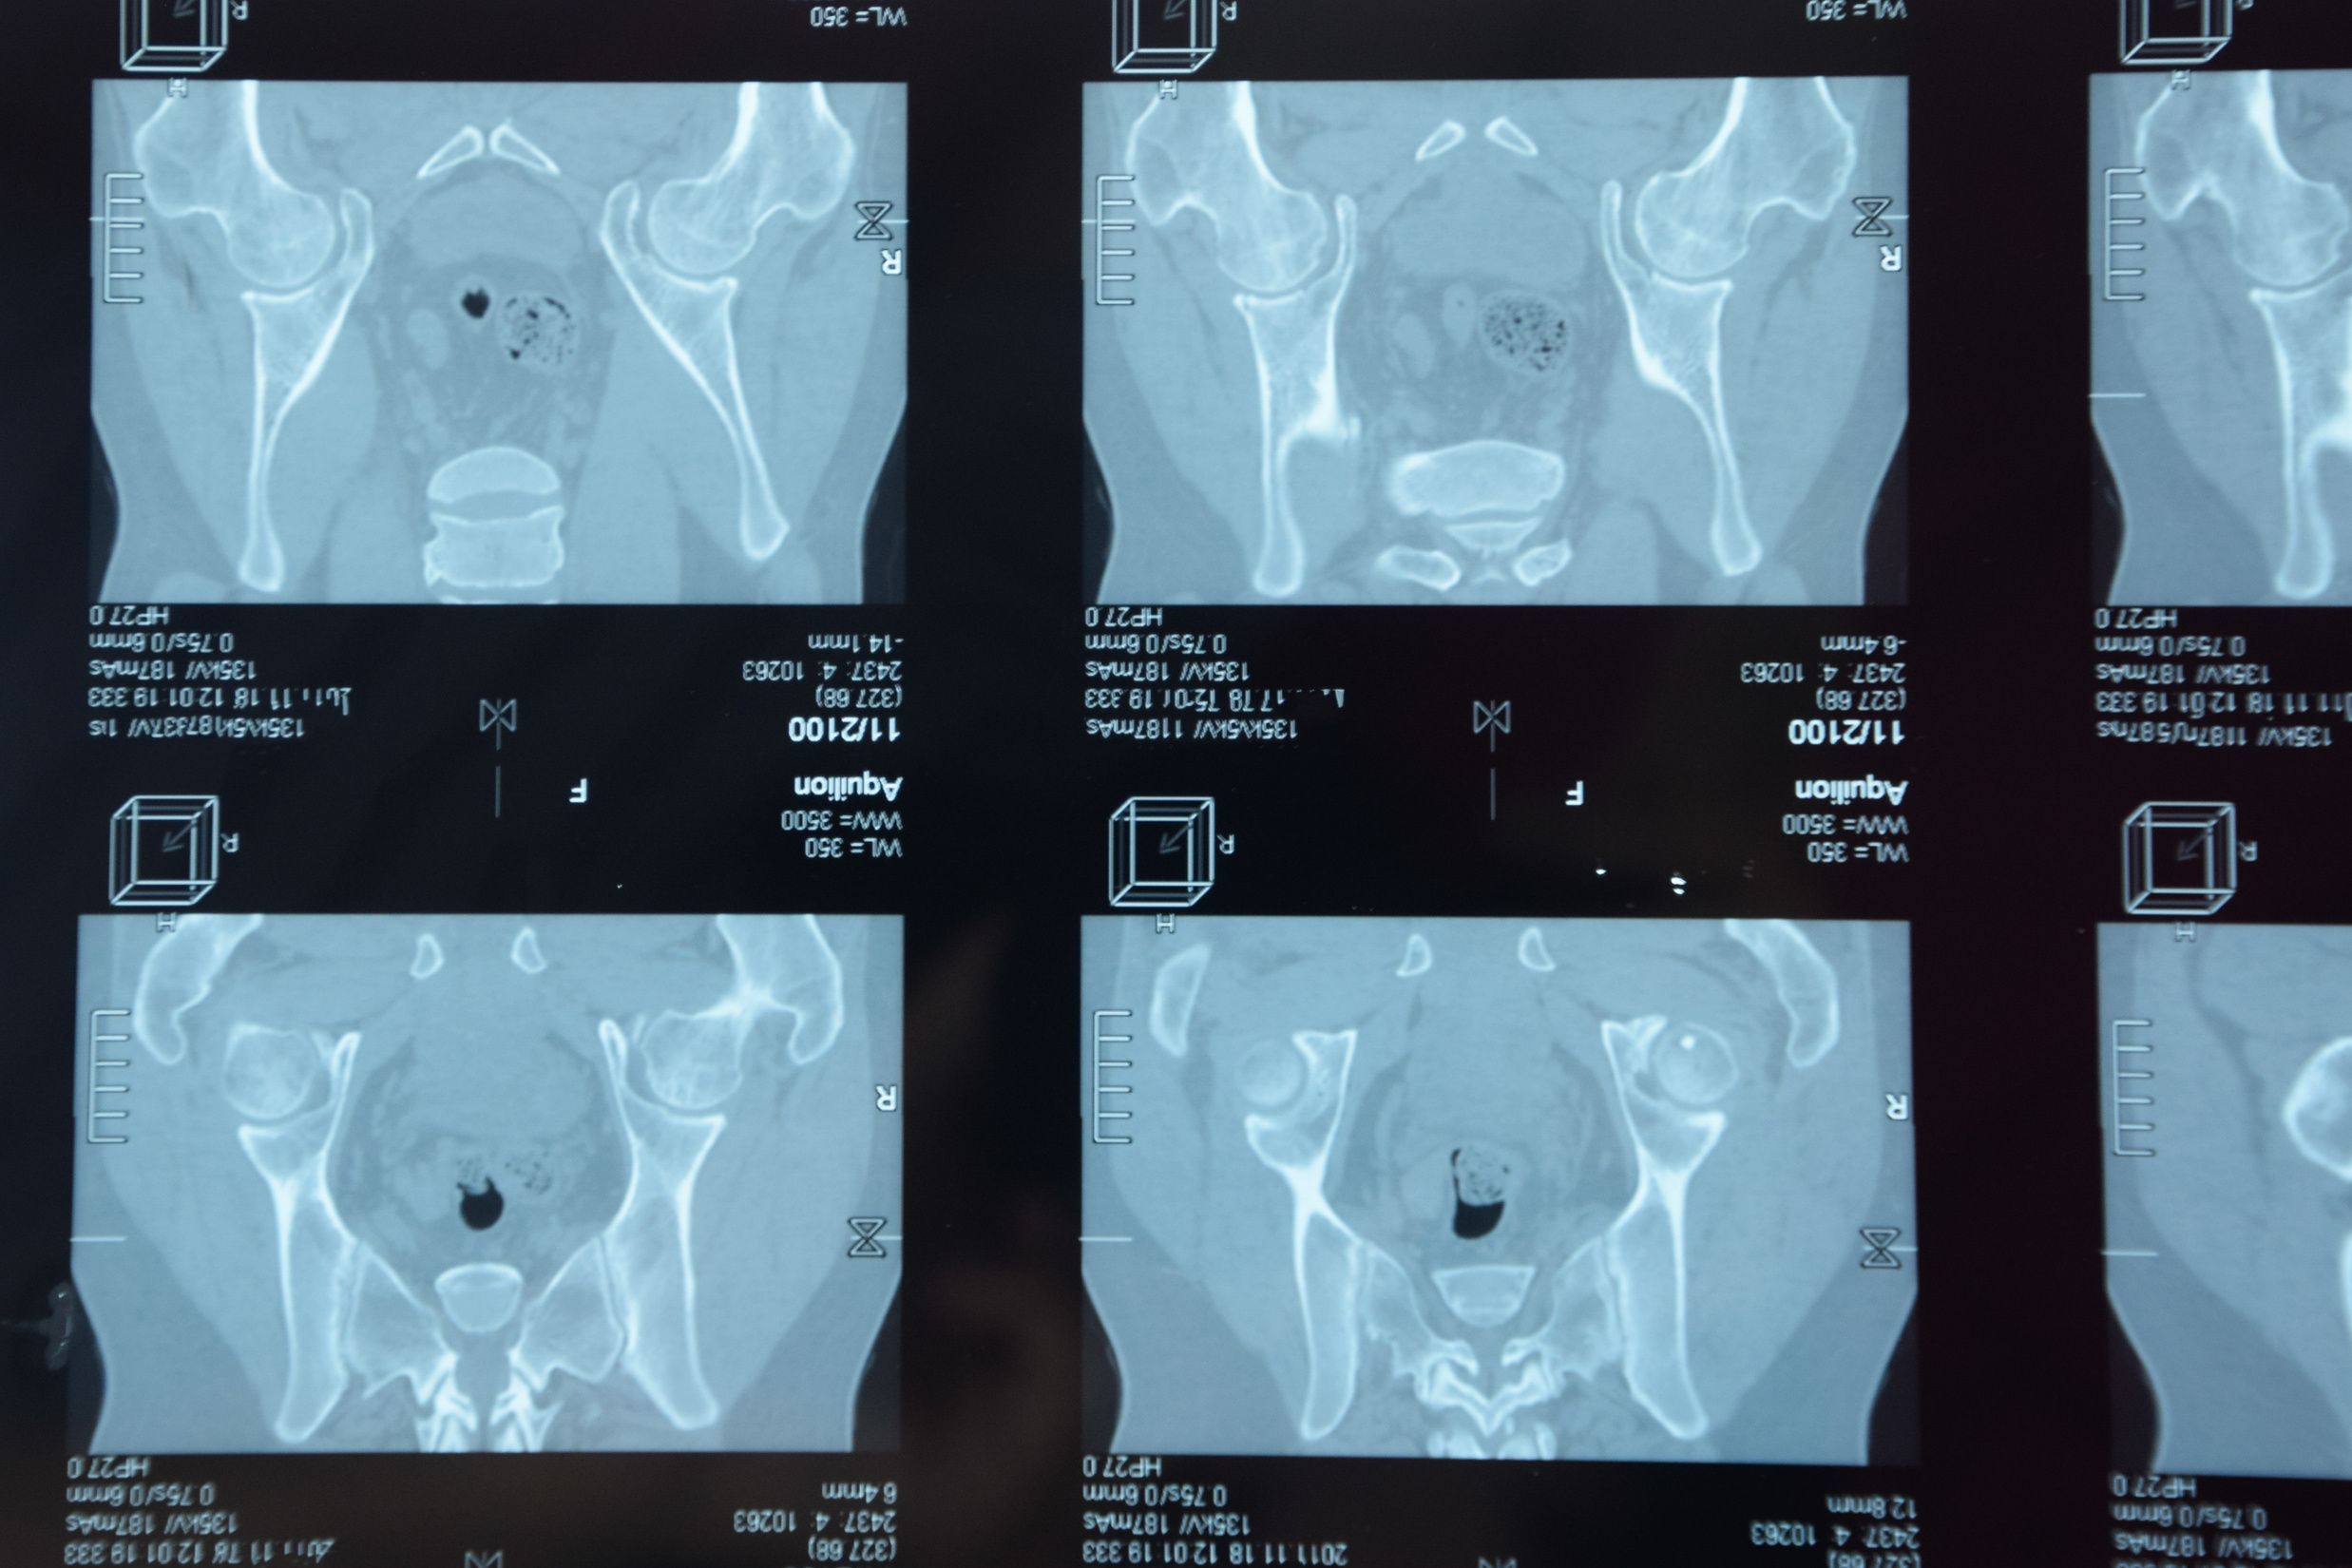

In this slideshow, we highlight 12 recommendations for assessing MRI lesions on the sacroiliac joints of patients with spondyloarthritis. The recommendations were made by the Assessment of Spondyloarthritis International Society (ASAS) MRI working group and published in the British journal Annals of the Rheumatic Diseases earlier this year.

An international physician group writing in the British journal Annals of the Rheumatic Diseases, has updated recommended parameters that constitute lesions in the sacroiliac joints of patients with spondyloarthritis. The definitions of capsulitis, enthesitis, fat lesion and erosion were revised and new definitions were developed for joint space enhancement, joint space fluid, fat metaplasia in an erosion cavity, ankylosis and bone bud.